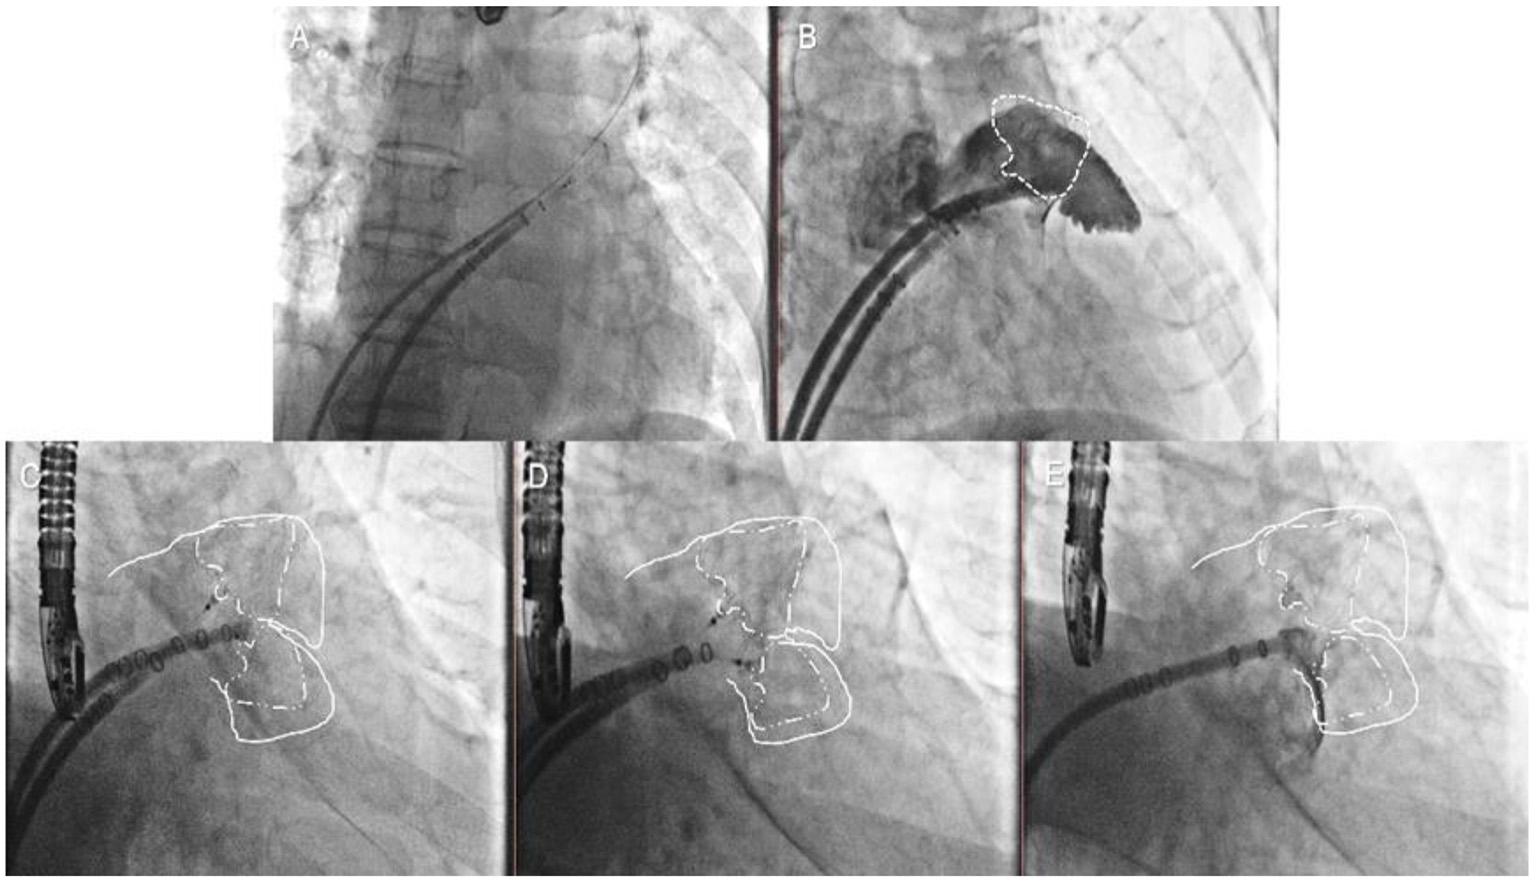

In the other cases, the first occluder was completely released after the PASS criteria had been met. The pigtail catheter with the access sheath was delivered carefully to the uncovered lobe, and selective angiography was performed (Figure 4, Step 5). The second-implantation step was similar to the first one but performed with more caution (Figure 4, Step 6). The second tug-test was performed with the second device (Figure 4, Step 7). The second device was released after the PASS criteria evaluation (Figure 4, Step 8).

Figure 4

Single-sheath strategy. Step 5 (A) selective angiography of the second lobe was performed after the first device was released; Step 6 (B) the second Watchman device was chosen according to the uncovered lobe; Step 7 (C) the second tug test was performed carefully with the second devices; Step 8 (D) the second device was released after the PASS criteria had been met with both devices.